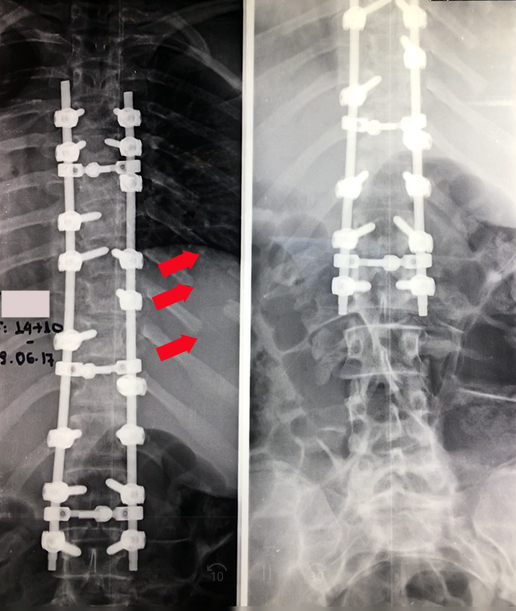

Εικόνα 10  Προσθιοπισθία άμεσος μετεγχειρητική ακτινογραφία

Το σκολιωτικό κύρτωμα έχει διορθωθεί με την εφαρμογή συστήματος σπονδυλοδεσίας, που περιλαμβάνει διαυχενικές βίδες, ράβδους και εγκάρσια συνδετικά των ράβδων. Τα βέλη δείχνουν τα σημεία στα οποία έγινε η αφαίρεση τμήματος των πλευρών (πλευροπλαστική) ώστε να μειωθεί ο θωρακικός ύβος.

Εικόνα 11, (α, β)  Mετεχγειρητική Προσθιοπισθία (α) και Πλαγία (β) ακτινογραφία της Α.Α.

Το θωρακικό σκολιωτικό κύρτωμα είναι 5 μοίρες